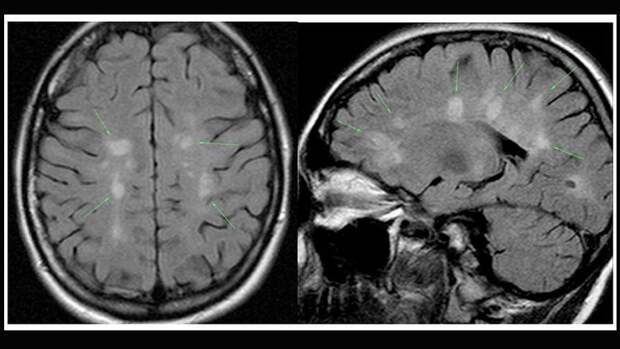

Говоря о симптомах, врачи отмечают, что диагностировать рассеянный склероз на основании одних лишь жалоб нельзя. Для постановки точного диагноза требуется комплексное обследование. В частности, МРТ головного и спинного мозга, которая может выявить участки повреждения нервных волокон - так называемые бляшки. Изменения при рассеянном склероза затрагивают всю центральную нервную систему и более чем у 90% больныхопределяются не только в головном, но и в спинном мозге.

Wikimedia Commons

Wikimedia Commons

Между тем, медики все же рекомендуют внимательно относиться к наиболее грозным симптомам, которые могут указывать на рассеянный склероз. Как правило, к ним относят шаткость походки, нарушение координации движений, слабость в конечностях, головокружение, выпадение полей зрения - и центрального и периферического.